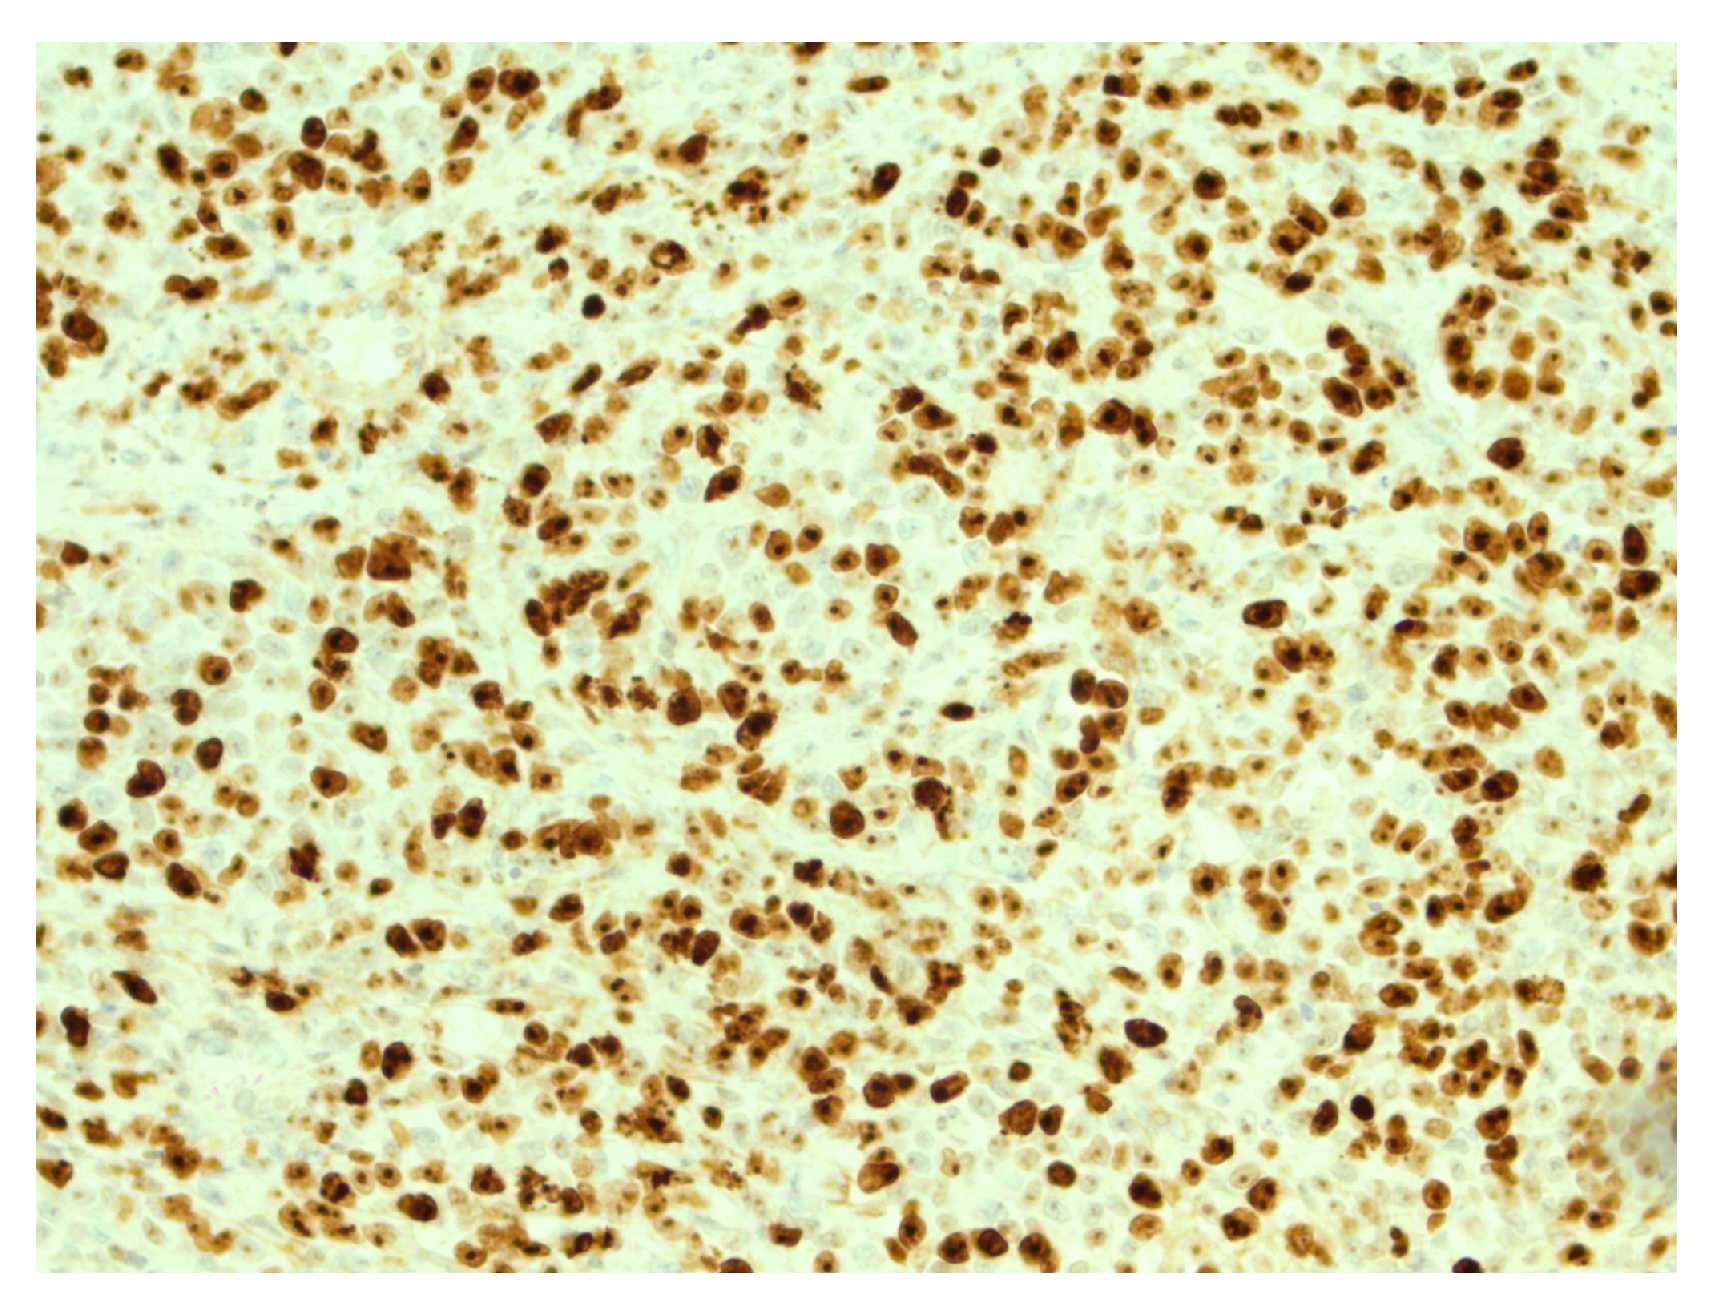

Figure 5.

High expression of Ki67 in tumor cells. IHC, original magnification ×200.